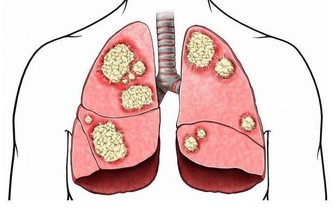

心腦血管疾病患者由於血管壁彈性降低,流向大腦的血液量減少,導致大腦缺血缺氧。當大腦缺血缺氧時,人就會哈欠連連,因為打哈欠能使腦細胞的供血供氧能力得到暫時的改善。而長期高血壓等心腦血管患者,由於動脈硬化程度較高,全身血管彈性變差,特別是一些小血管壁越來越薄,甚至個別地方產生「鼓包」(即微小的動脈瘤)現象,一旦血壓驟然升高,容易導致腦血管管壁破裂,形成出血性腦卒中。高血壓可使腦血管動脈硬化的發展加速、加重,血管硬化造成的血管狹窄和硬化的血管壁內形成的斑塊破裂,引起的血栓則會造成血管的堵塞,從而引發缺血性卒中。

據臨床統計,70%~80%的缺血性腦卒中患者,在發病前一周左右會因大腦缺血缺氧而頻頻出現打哈欠的現象。因此,有高血壓等心腦血管病史的患者無原因出現頻繁打哈欠時,應及早到醫院檢查治療。